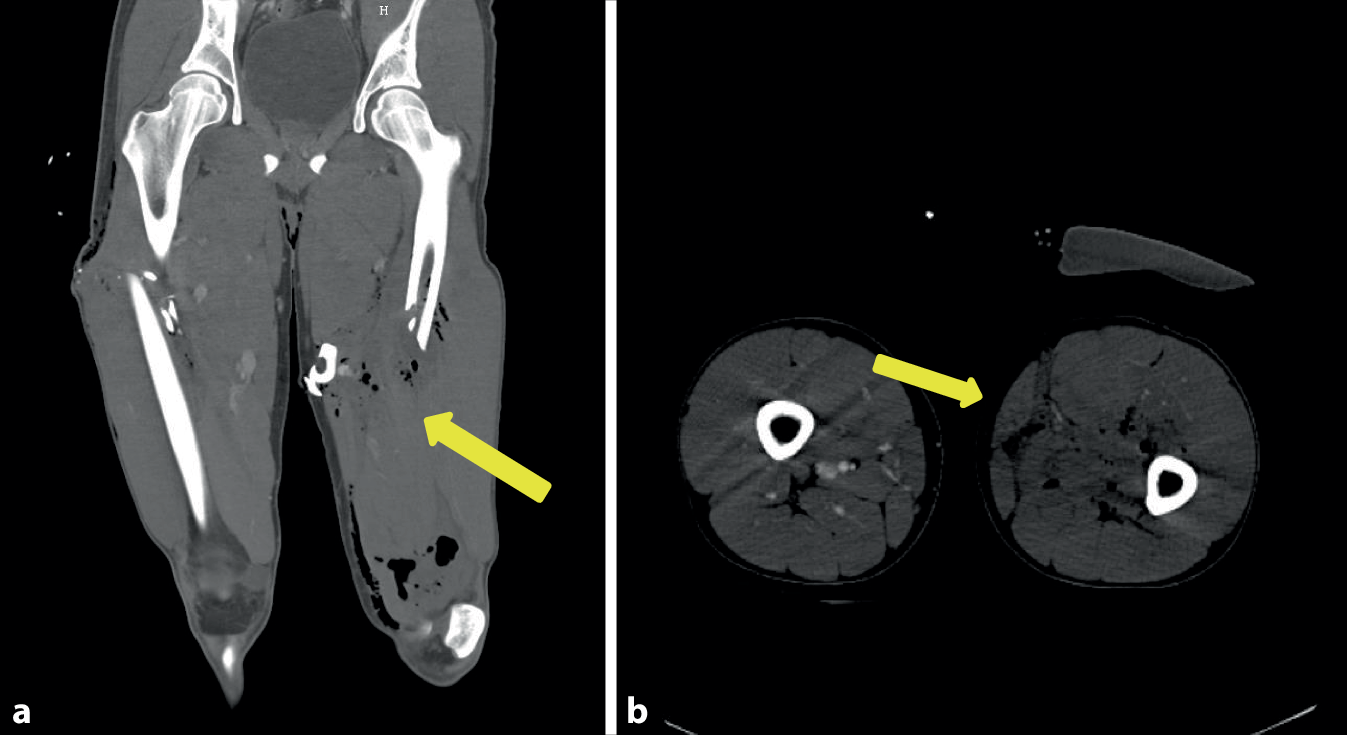

Im Rahmen eines Sturzes erlitt eine 92-jährige Patientin eine pertrochantäre Femurfraktur rechtsseitig, die durch eine geschlossene Reposition und Osteosynthese mittels proximalen Femurnagels Antirotation (PFNA)-Verriegelungsnagel (Fa. DePuy Synthes, Oberdorf, Schweiz) rechts versorgt wurde. Bei guter physischer und psychischer Compliance wurde die Patientin postoperativ frühzeitig mobilisiert und in die Häuslichkeit entlassen. Die Vorstellung in der Gefäßchirurgie erfolgte nach 2 Monaten aufgrund einer peripheren arteriellen Verschlusskrankheit (pAVK) Stadium IV mit Zehennekrosen rechts. Die Diagnostik mittels farbkodierter Duplexsonographie zeigte eine ca. faustgroße echoleere Raumforderung neben dem Schenkelhals mit einer pulssynchronen Verwirbelung im Sinne eines Pseudoaneurysmas (Abb. 2a). Die CTA ergab neben einer ausgeprägten Unterschenkel-pAVK rechts ein monströses Pseudoaneurysma der A. profunda femoris rechts mit ausgeprägter perifokaler Verkalkung (Abb. 2b). Bereits in einer Nativröntgenaufnahme ist medial des Schenkelhalses eine schalenförmige Verkalkungsstruktur zu sehen (Abb. 2c). Aufgrund der begleitenden kritischen Ischämie des rechten Unterschenkels erfolgte der kombinierte Eingriff der offenen Resektion des Pseudoaneurysmas und Ligatur des perforierten Profundaastes (Abb. 2d) sowie die begleitende Ballonangioplastie des Unterschenkels, worunter es zu einer Stabilisierung der pAVK Stadium IV rechtsseitig kam. Der genaue Mechanismus der Entwicklung des Pseudoaneurysmas verblieb letztlich nicht völlig geklärt, da der Operationsbericht keinen Hinweis auf einen untypischen Operationsverlauf ergab.

Abb. 2

Fall 2: Pseudoaneurysma der A. profunda femoris rechts. a Farbkodierte Duplexsonographie des Pseudoaneurysmas mit typischem Farbwechsel (gelber Pfeil), b CT-Angiographie mit Nachweis des Pseudoaneurysmas der rechten Inguinalregion (gelber Pfeil), c Nativröntgen der mit einem PFN-Nagel versorgten pertrochantären Fraktur mit zirkulärer Verkalkung (gelber Pfeil), d intraoperative Darstellung der Pseudoaneurysmahöhle und des verletzten Profundaastes (gelber Pfeil)